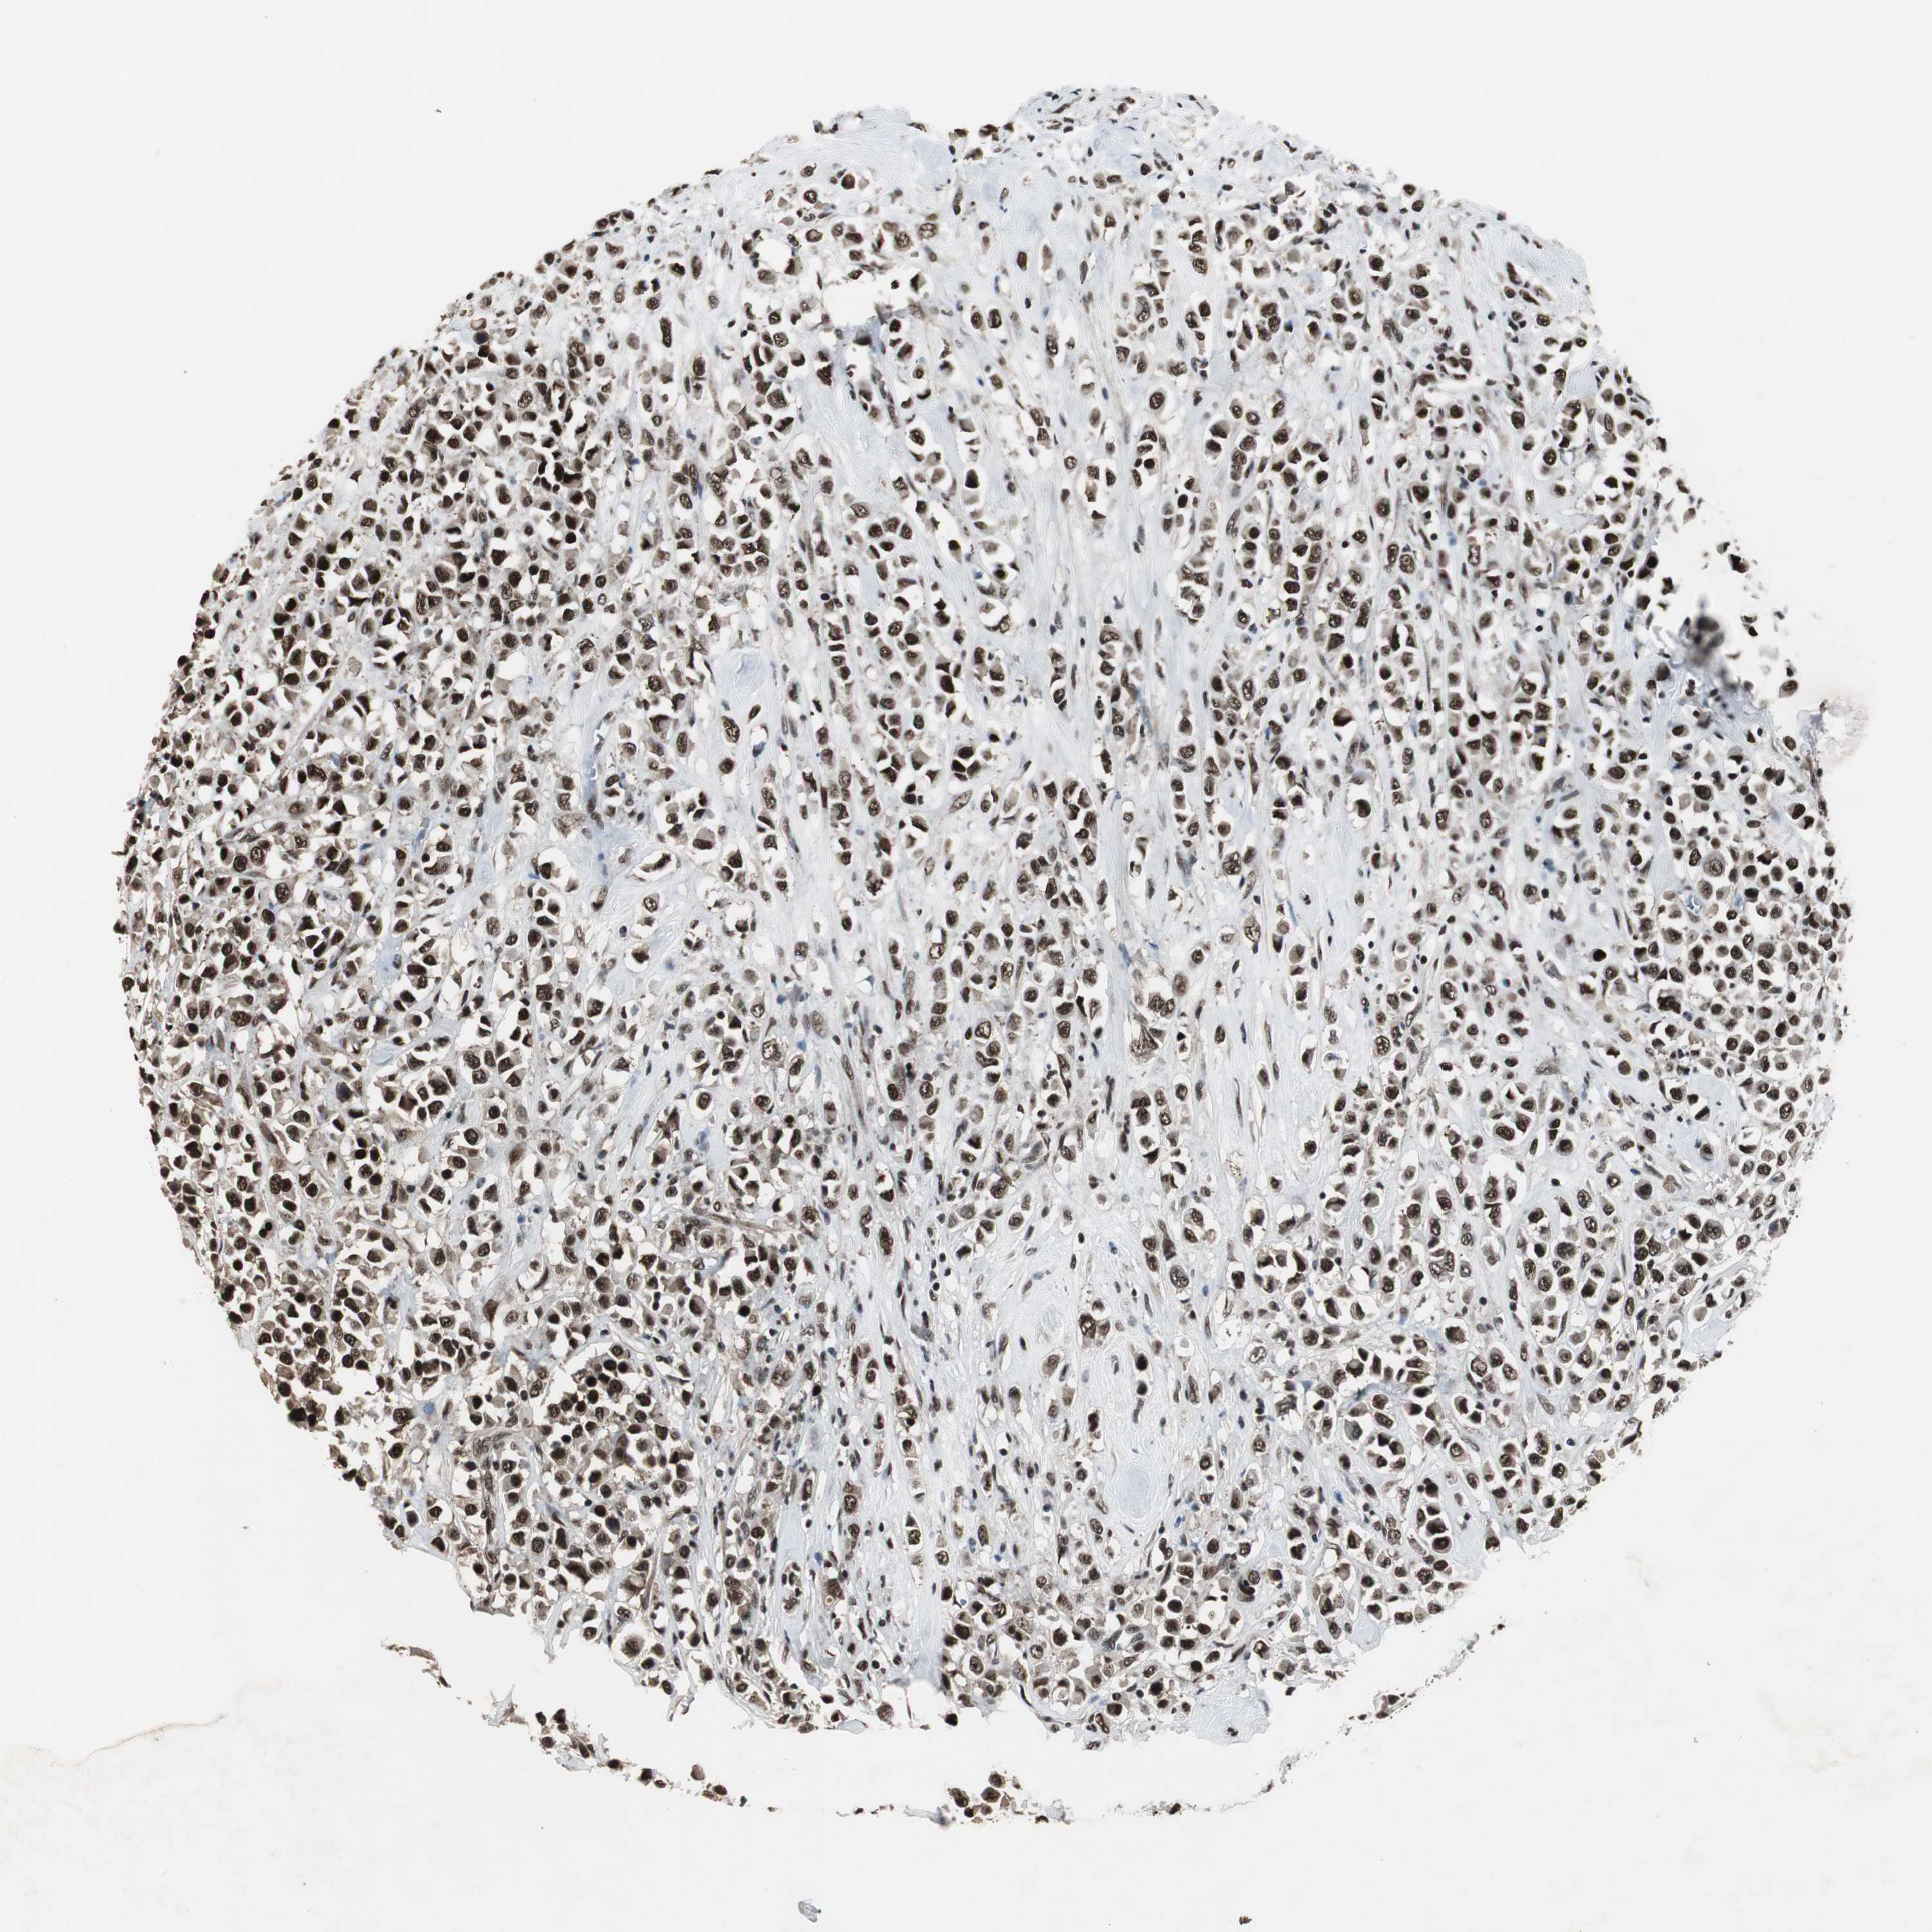

CANCER BREAST CANCER Show tissue menu

BRCA TCGA BRCA VALIDATION PROTEIN EXPRESSION